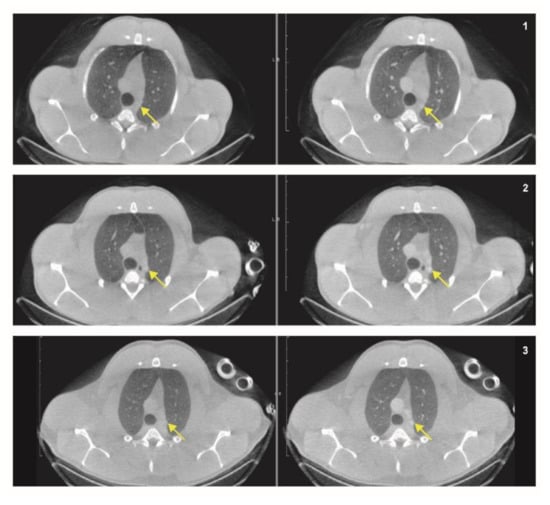

3.4.1. ROI Definition

3.4.2. Anatomical and Functional Results